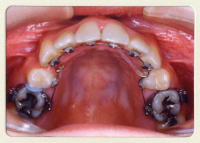

使用する装置

目立ちにくいセラミックブラケットを使用します。

咬み合せの状態によっては、下の歯にメタルブラケットを使用します。